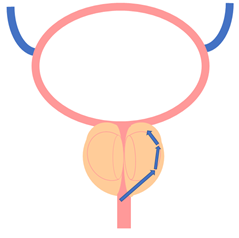

전립선 비대증은 남성에서 발생하는 일종의 전립선 증상으로, 전립선이 지나치게 커지는 현상을 가리킵니다. 전립선은 남성의 방광 하단에서 요도를 둘러싸고 있는 작은 밤알 모양의 기관으로, 정액의 구성 성분 중 일부를 생성합니다.

청소년기에는 남성 호르몬의 영향으로 정상적인 성인 크기로 성장하며, 40세까지는 대부분 안정된 크기를 유지하다가 노화 과정에서 커질 수 있습니다. 크게 커진 전립선은 요도를 압박하며 이로써 소변 배출에 어려움을 초래하고 다른 다양한 증상을 유발합니다.

전립선 비대증은 전립선이 커져서 소변이 나오는 길인 요도를 압박하여 소변 흐름을 방해하는 상황을 나타냅니다. 처음에는 방광 근육이 강하게 수축하여 요도가 좁아져도 증상이 크게 나타나지 않을 수 있지만, 시간이 지남에 따라 증상이 나타납니다.